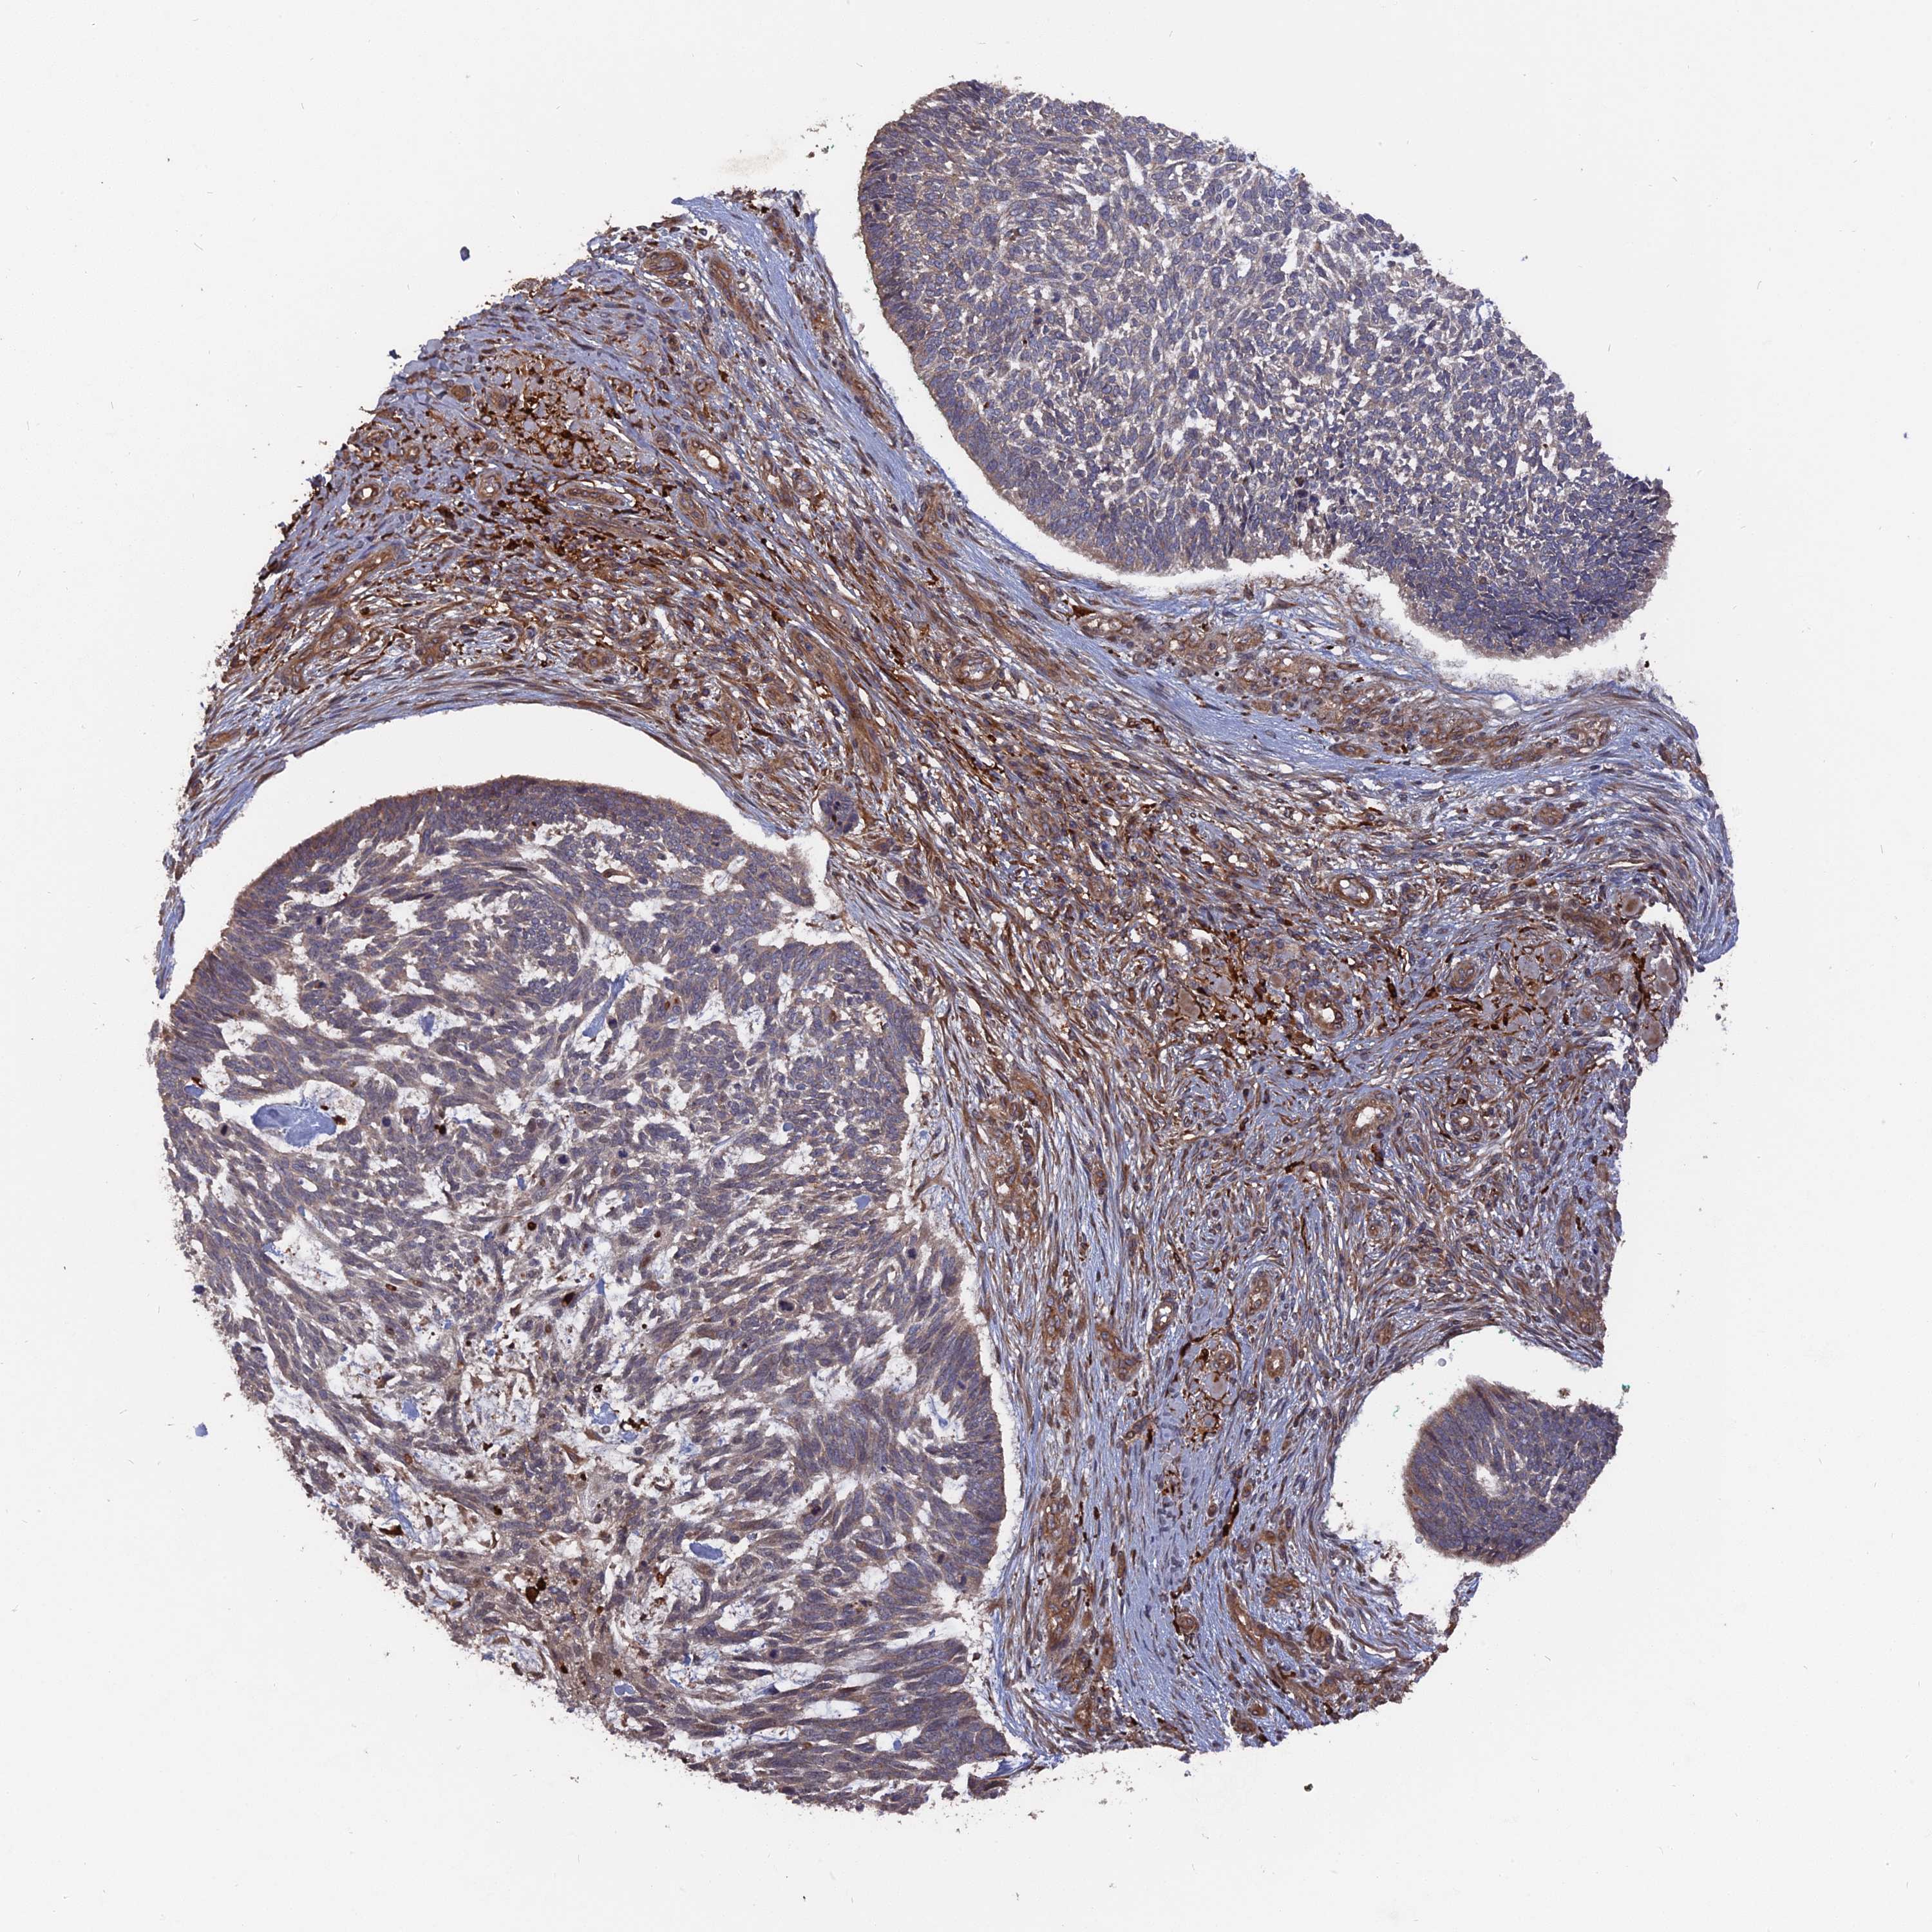

SKIN CANCER - Protein expressioni

A mouse-over function shows sample information and annotation data. Click on an image to view it in a full screen mode. Samples can be filtered based on level of antibody staining by selecting one or several of the following categories: high, medium, low and not detected. The assay and annotation is described here.

Each image is clickable and will lead to virtual microscopy that enables deeper exploration of all samples and also displays staining intensity scores, fraction scores and subcellular localization as well as patient and tissue information for each sample.

Antibody HPA041745

Staining

High

Medium

Low

Not detected

Intensity

Strong

Moderate

Weak

Negative

Quantity

>75%

75%-25%

<25%

None

Location

Nuclear

Cytoplasmic/membranous

Cytoplasmic/membranous,nuclear

Squamous cell carcinoma, NOS

Squamous cell carcinoma, metastatic, NOS